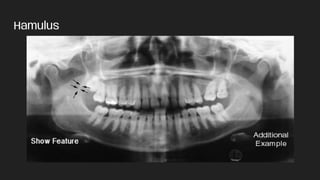

● Hamulus

Hamulus